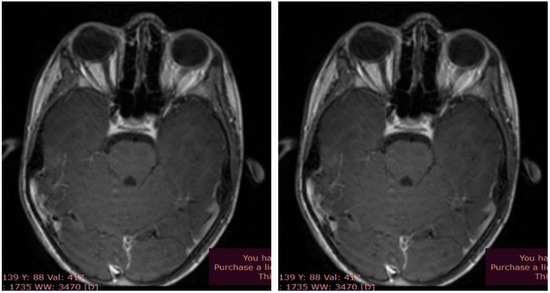

Cervical neck and brain MRI showed dimensional asymmetry at the level of the optic nerves (II), with a retro-ocular transverse diameter of 4.5 mm on the right side and 4 mm on the left side, but symmetric prechiasmatic areas, without native or post-contrast signal abnormalities. The imaging also revealed the existence of a retrovermian arachnoid cyst, paramedian on the left side with a diameter of 9/10 mm, and a minimal C5-C6 posterior disc bulge with discrete dural sac indentation, without discoradicular conflicts (Figure 2, A and B).

Figure 2. Brain MRI - optic nerves; (A) T2 sequence, native axial; (B) T1 sequence, axial contrast.

Although MRI is not necessary in most cases for diagnosing ON in children, it can reveal focal abnormalities of the anterior visual pathway [10]. Typical changes on MRI in studies dedicated to the orbit include thickening of the optic nerves on T1-weighted imaging and bright T2 signal along the optic nerve, which were also identified in our case.